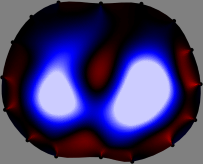

Figs. 3 and 4 compare the performance of the proposed FER method in (20) with the standard regularized least-squares method ((19) when \mathcal{R} is the identity matrix). The regularization parameter of the standard method was heuristically chosen for its best performance, and the parameter of the FER method was set to be one of three different values λ=0.05,0.2,𝜆0.050.2\lambda=0.05,0.2,\infty. The injection current was 1 mARMSRMS{}_{\tiny{\mbox{RMS}}} at 100 kHz, and the frame rate was 9 frames per second. The reference frame at t0subscript𝑡0t_{0} was obtained from the maximum expiration state. The measured data, 𝐕˙(tm)˙𝐕subscript𝑡𝑚\dot{\mathbf{V}}(t_{m}), represent the voltage differences between each time tmsubscript𝑡𝑚t_{m} and t0subscript𝑡0t_{0}. The blue regions, which denote where conductivity decreased by inhaled air, increased during inspiration and decreased during expiration. The FER method with λ=𝜆\lambda=\infty was clearly more robust than the standard method that produced more artifacts originated from the inversion process.

Figure 3: The reconstructed images of the conductivity change of the subject A by the standard regularized least square method and the proposed fidelity-embedded regularization (FER) method for three difference values λ=0.05,0.2,𝜆0.050.2\lambda=0.05,0.2,\infty. Here, the time step is 0.22 seconds (tm+2tm0.22subscript𝑡𝑚2subscript𝑡𝑚0.22t_{m+2}-t_{m}\approx 0.22).

Figure 4: The reconstructed images of the conductivity change of the subject B by the standard regularized least square method and the proposed fidelity-embedded regularization (FER) method for three difference values λ=0.05,0.2,𝜆0.050.2\lambda=0.05,0.2,\infty. Here, the time step is 0.55 seconds (tm+5tm0.55subscript𝑡𝑚5subscript𝑡𝑚0.55t_{m+5}-t_{m}\approx 0.55).